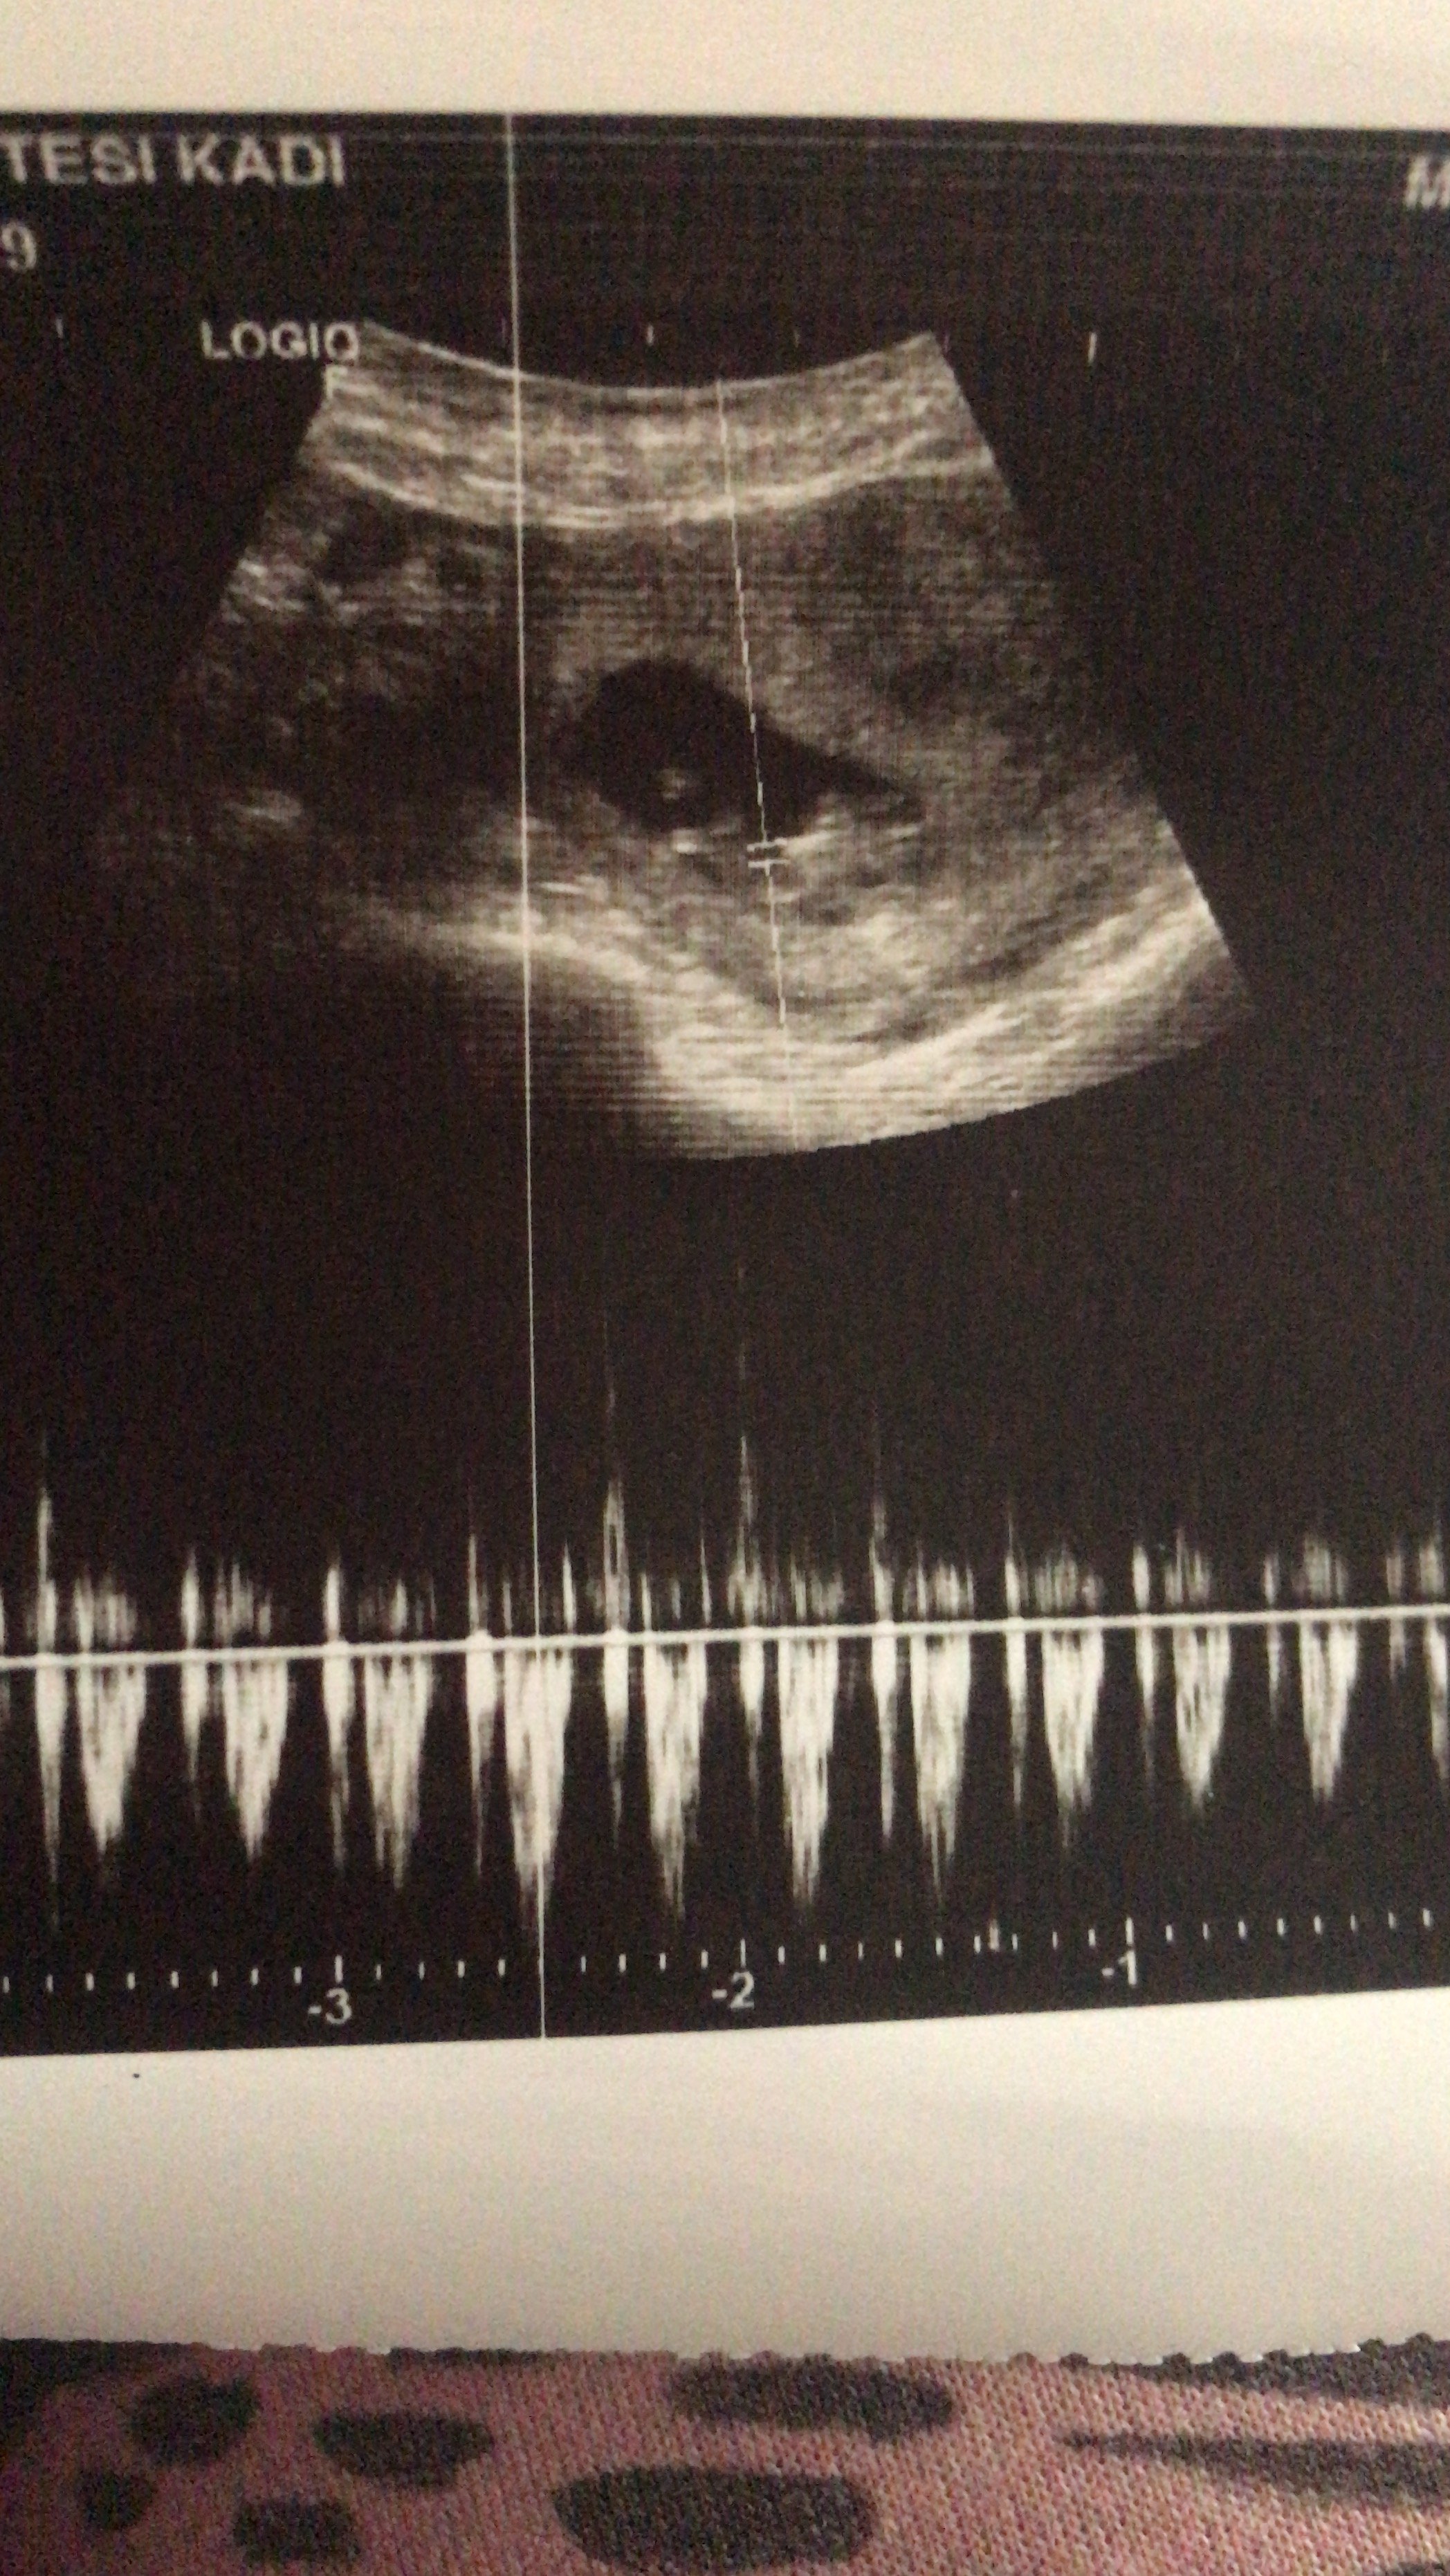

G gmzgrr Yeni Üye Üye 19 Kasım 2022 #177 SadmiN' Alıntı: Malesef hayatım çok sisli ve buğulu bir şey anlaşılmıyor aşka resimler geldikçe ekleme yap lütfen değerlendirme yapalım. Genişletmek için tıkla ... Ekli dosyalar 4586FF8E-C1EA-4B30-A92D-FE046762C308.jpeg 1,1 MB · Görüntüleme: 206

SadmiN' Alıntı: Malesef hayatım çok sisli ve buğulu bir şey anlaşılmıyor aşka resimler geldikçe ekleme yap lütfen değerlendirme yapalım. Genişletmek için tıkla ...

SadmiN ♥ Evli Mutlu Çocuklu ♥ Yönetici 20 Kasım 2022 #178 Selamlar bu resim net hayatım kız görünüyor. İnşallah yanılmam 🙂

SadmiN ♥ Evli Mutlu Çocuklu ♥ Yönetici 20 Kasım 2022 #180 Tinimini' Alıntı: Benim mi 😉 Genişletmek için tıkla ... Yok bitanem @gmzgrr arkadaşımızın eklediği resim hayatım seninki net değildi.

Tinimini' Alıntı: Benim mi 😉 Genişletmek için tıkla ... Yok bitanem @gmzgrr arkadaşımızın eklediği resim hayatım seninki net değildi.